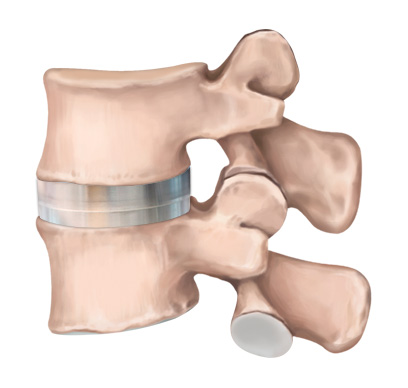

STEP 03

인공디스크 삽입

척추 움직임이 정상 디스크와 유사하여 움직임이 매우 자유롭습니다.

경추 인공디스크 치환술 후 자유로운 목 움직임